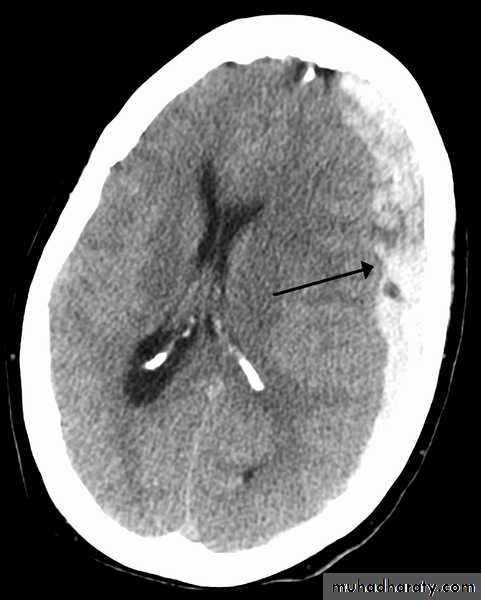

Acute Intra cerebral hematoma

CT finding :Hyper dense area , surrounded by edema , any where within the brain parenchyma.

Shifting of the midline

Compression of the ipsi lateral ventricle .

Associated with infarction , # , trauma concussion , tumor …..